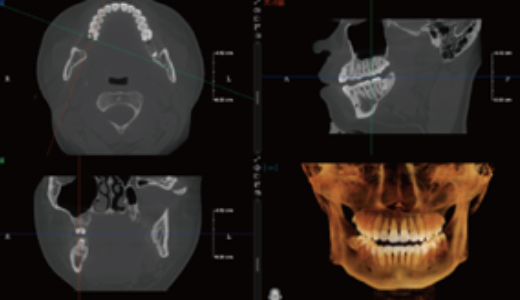

Visualização 3D do Seio Maxilar

Gera automaticamente a estrutura 3D do seio maxilar.

Permite uma observação clara da morfologia do seio e ajuda a avaliar os riscos cirúrgicos em implantes maxilares.

Auxilia na avaliação do volume de enxerto em elevação do seio maxilar

Planeamento Virtual de Implantes

Permite a simulação de procedimentos de implantes (implante + pilar + coroa), ajudando a selecionar o implante mais adequado.

Fornece alertas de proximidade ao canal nervoso, aumentando a segurança cirúrgica.

Facilita a comunicação entre médico e paciente, permitindo ao paciente visualizar claramente o procedimento de implante planeado.